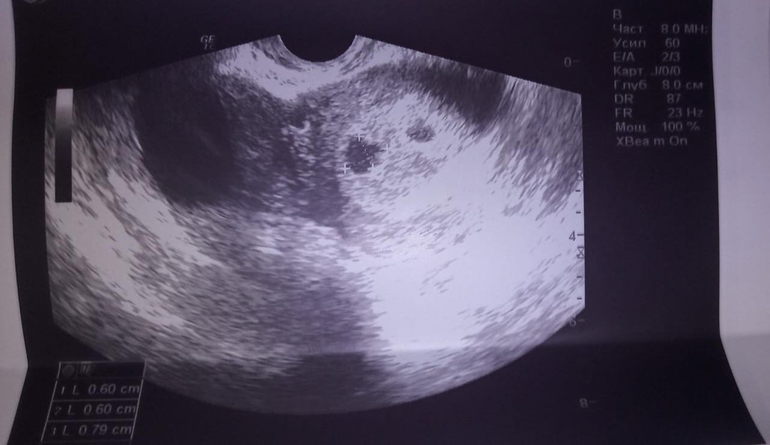

Отдам даром детские товары/аптека.Девочки, у кого так было, очень переживаю. В 5,5 недель ходила на УЗИ, чтобы подтвердить маточную беременность, увидели 2 плодных яйца. Одно нормальной формы, другое деформированное. Жёлтое тело одно. Врачи говорят, что второе плодное яйцо скорее всего развиваться не будет. Очень жду повторного УЗИ в 7,5 недель - 25.05.